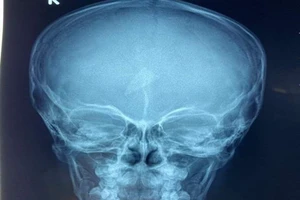

Sức khoẻ bé trai 2 tuổi bị mẹ ruột cùng nhân tình đánh đến nguy kịch

06/05/2026 13:37

Lời khai của người mẹ và nhân tình đánh bé trai 2 tuổi đa chấn thương

06/05/2026 12:29